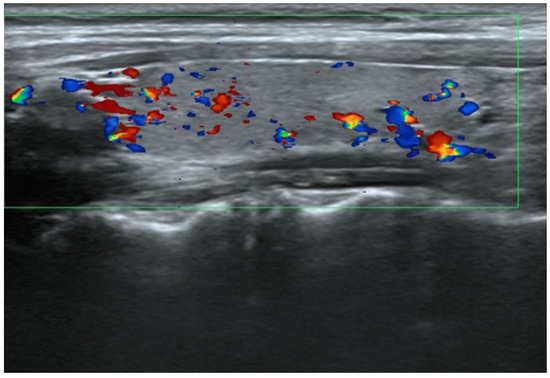

3. Case Report